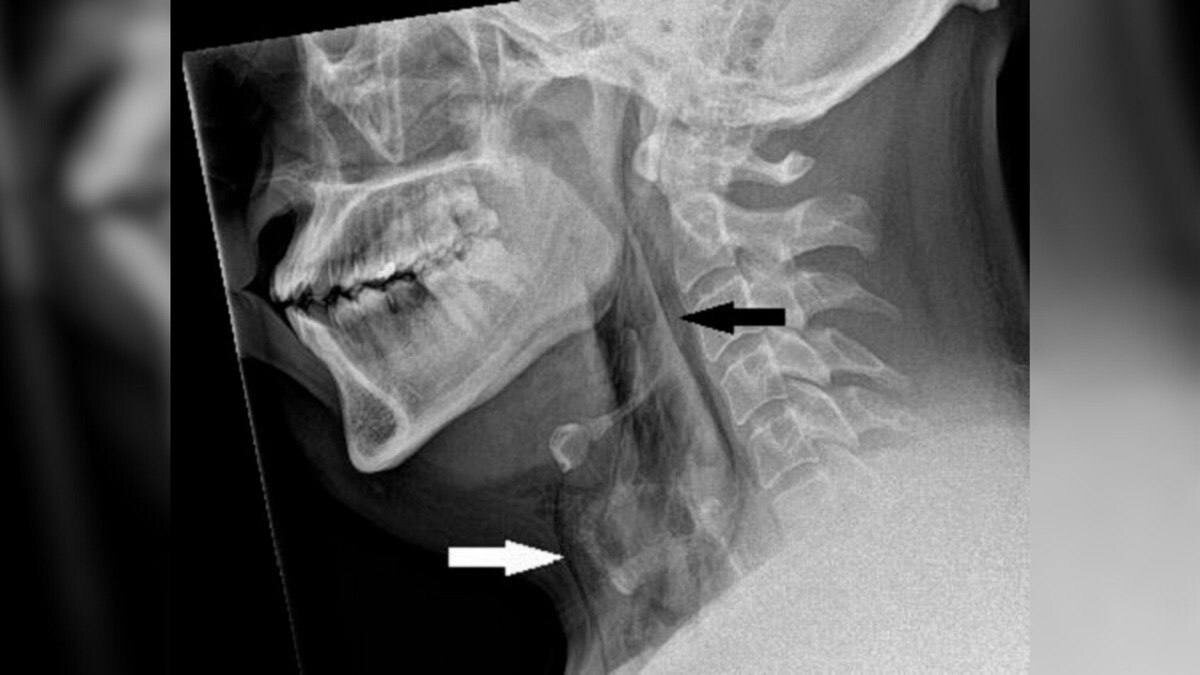

В больнице мужчине заявили: он порвал горло. Но воздух свободно поступал под кожу, и пациент мог дышать сам. К большому везению, обошлось даже без операции, врачи дали обезболивающих и отпустили мужчину. Вскоре всё зажило само.

Когда человек чихает, в горле растёт давление. А если сдержать чих, то давление вырастет в 20 раз! Не делайте так.